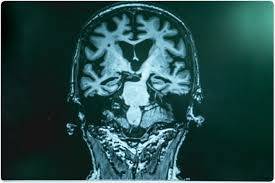

치매는 단순히 노화에 따른 자연스러운 현상이 아니라 뇌의 구조와 기능이 점점 손상되어 일상생활에 심각한 어려움을 겪게 되는 질환입니다. 특히 조기 예방이 중요한데, 많은 사람들이 인지하지 못한 일상 속 습관들이 오히려 치매 위험을 높일 수 있다는 사실이 최근 다양한 연구에서 확인되고 있습니다. 오늘은 과학적으로 입증된 ‘의외의 치매 유발 습관’ 다섯 가지를 살펴보겠습니다.